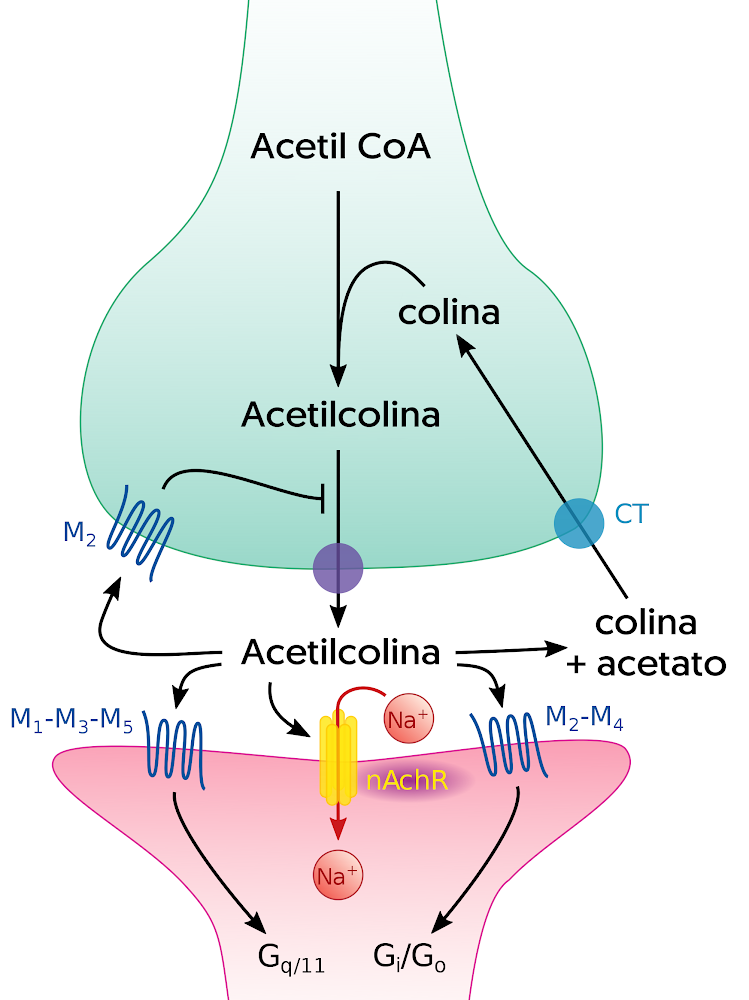

Se trata de neurotransmisor crucial en el sistema nervioso central (SNC) que desempeña un papel significativo en una amplia gama de funciones cognitivas y neurobiológicas. Para su síntesis, se requiere la acción de la enzima colina acetiltransferasa, que utiliza como sustratos la colina y el acetil-CoA. Una vez sintetizada, se almacena en vesículas en las terminales presinápticas, listas para su liberación en respuesta a estímulos adecuados (Kandel y Schwartz, 2000).

Por otro lado, su liberación se lleva a cabo mediante un proceso conocido como exocitosis, en el cual las vesículas liberan su contenido en el espacio sináptico. Este proceso es desencadenado por la llegada de un potencial de acción a la terminal presináptica. En el momento de ser liberada en la hendidura sináptica, se une a los receptores colinérgicos presentes en la membrana postsináptica.

Los receptores colinérgicos son proteínas ubicadas en las células del sistema nervioso que se unen a la acetilcolina. Existen dos tipos principales de receptores colinérgicos:

- Receptores nicotínicos: Son canales iónicos que generan respuestas rápidas y excitatorias.

- Receptores muscarínicos: Están acoplados a proteínas G y generan respuestas más lentas y variadas.

Cuando hablamos de modulación, nos referimos a la capacidad de regular la actividad de este neurotransmisor en el cerebro. Es posible influir en la acetilcolina mediante el uso de fármacos que actúan como agonistas o antagonistas de los receptores colinérgicos. Esto se debe a que, tales fármacos, pueden potenciar o bloquear su acción en las células nerviosas.

Los agonistas colinérgicos, al activar los receptores colinérgicos, aumentan la actividad de la acetilcolina, lo que puede tener efectos beneficiosos en el tratamiento de trastornos de la memoria y el aprendizaje.

Con esto, los antagonistas colinérgicos bloquean los receptores colinérgicos, disminuyendo su actividad. Por lo que, los fármacos pueden ser útiles en ciertas situaciones clínicas donde se requiere reducir la actividad colinérgica.